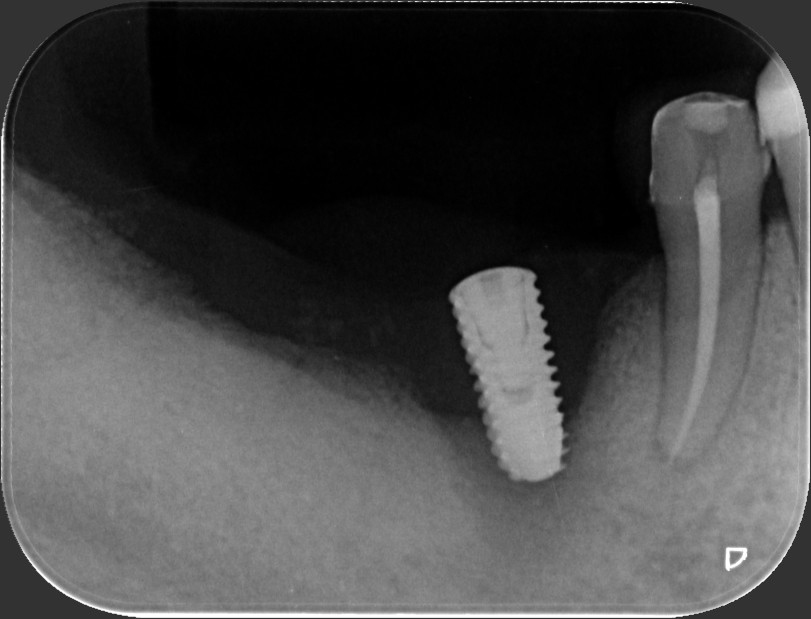

如果植體後方位置過深,加上牙齦萎縮、螺紋暴露,就更容易堆積牙菌斑,植體結構恐淪為「細菌的溜滑梯」,使炎症沿著螺紋向下蔓延。對有牙齦萎縮或清潔不佳的患者而言,植體周圍炎的威脅恐將增加。相較之下,All-On-4只需在上顎植入五顆、下顎植入四顆植體(或稍作調整),即能支撐整座牙橋。植體數量雖減少,但並不代表就能高枕無憂;真正決定植牙長期穩定的,仍在於患者的術後保養。

對於同時患有嚴重牙周病與多顆缺牙的患者,All-On-4是否為最適合的療程?王柏凱醫師解釋,若上顎僅剩四顆以下健康牙齒、下顎兩顆以下,且牙周狀況堪憂,往往會建議全面拔除剩餘牙齒,以防將來持續發炎或鬆脫。由於牙周病是牙齒周圍組織的疾病,當自然牙都被去除後,理論上就不會再有傳統牙周病的問題。

不過,人工植體依然可能罹患「植體周圍炎」,其發病機制與牙周病相似,如同「植牙版牙周病」,兩者對口腔的影響皆是細菌滋生、侵害周邊骨組織。因此,就算透過All-On-4一勞永逸解決了多顆缺牙並「避免」牙周病問題,患者仍需每日勤加清潔,徹底做好防範。吸菸、飲食習慣、個人體質或免疫力等因素也會影響植牙的長期穩定性。